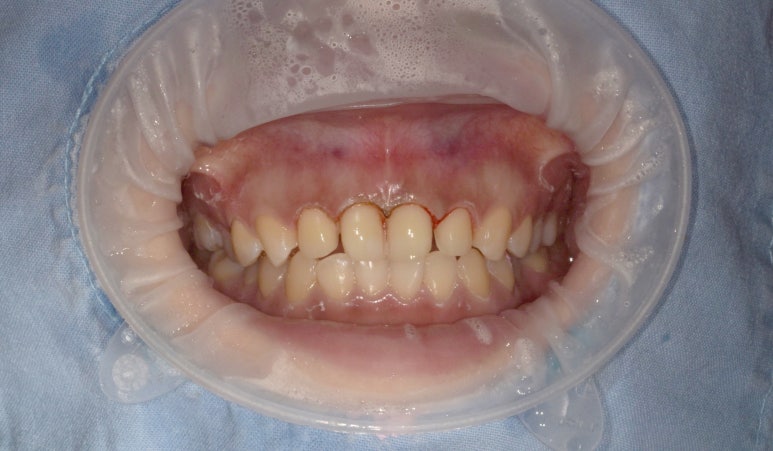

너무 적나라한 사진이라... 부끄럽네요

촬영일자: 2023-05-12

제가 양쪽 대문니 옆 치아(상악 측절치)가 살짝 작은 상태이고

잇몸도 다른 부분보다 조금 더 내려와있어서

잇몸성형을 통해 라미네이트하는 치아의 잇몸 라인을 다듬어주고,

치아미백도 진행해 치아 색상을 톤업시켰습니다.